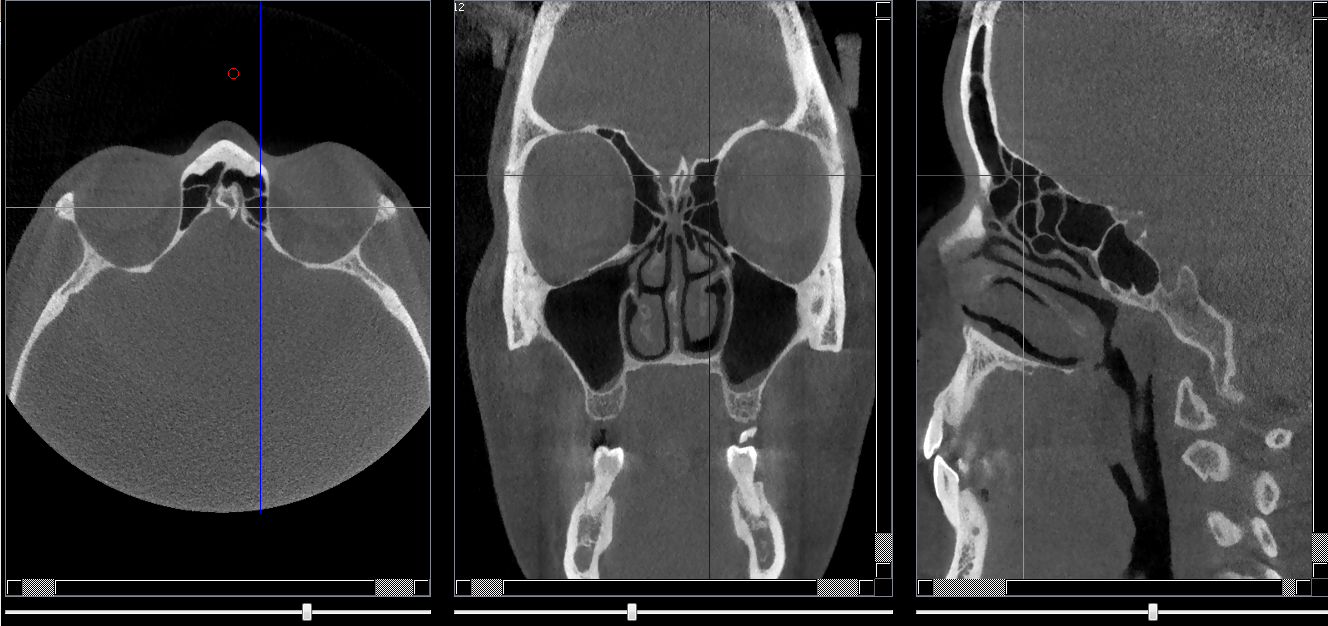

Fissure orbitaire supérieure

Repères anatomiques

- Coupe transversale

- Début : Cornet nasal sup

- Fin : Partie sup du crista galli

- Coupe frontale

- Début : Partie post du processus zygomatique

- Fin : Partie ant du processus zygomatique

- Coupe saggitale

- Début : Crista galli

- Fin : Paroi de l'orbite